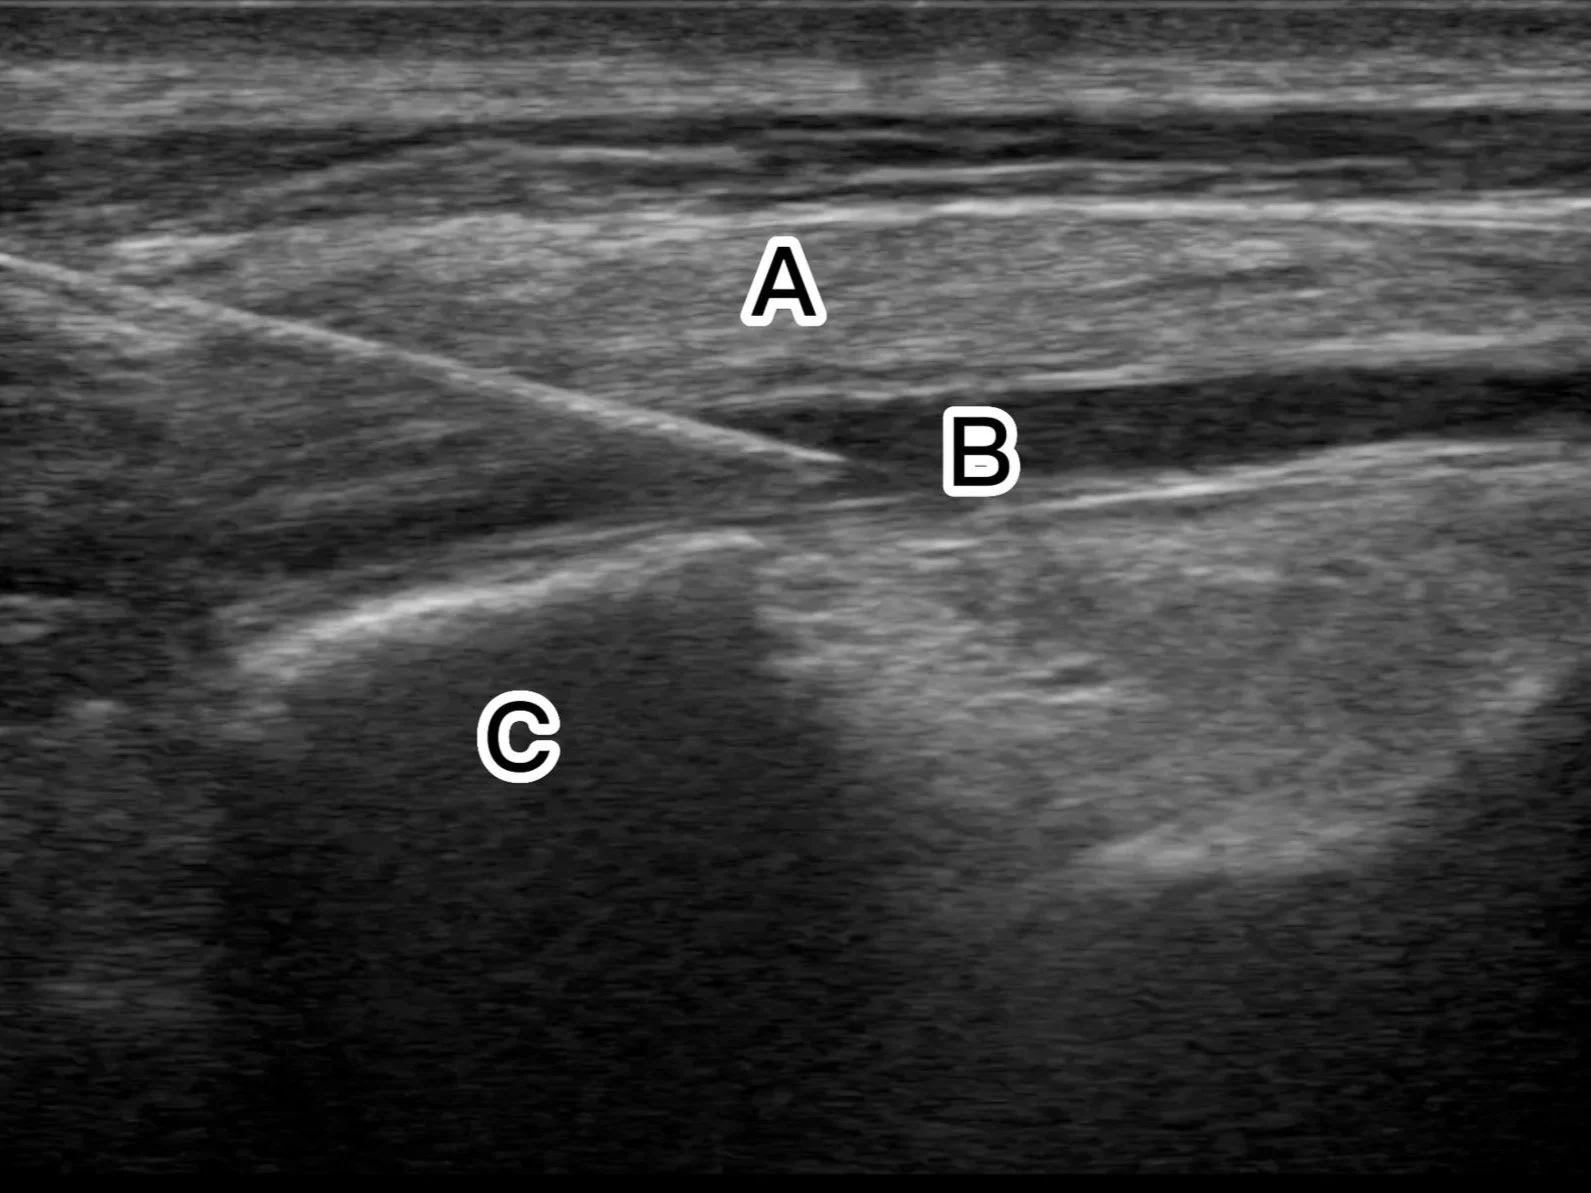

• A - Erector Spinae muscle

(Trapezius & rhomboid major muscles might be visualised too, visualised as a three layer muscle complex)

B - Local anaesthetic

C - Transverse Process

The linear (or curvilinear depending on the body habitus) probe is placed in a cranio-caudal orientation just medial to the scapula. It is usually at the level of the 5th rib or lower depending on the level of the rib fractures (as a plane block usually covers 3 rib levels cranial and caudal from the injection site level). This level could be located by counting down the ribs either manually, or with ultrasound visualisation.

Visualise the ribs which have a rounded contour and underlying pleura. Slide the probe medially towards parasagittal plane, and carefully look for transition of the rounded ribs to a tombstone/square-shaped transverse process (TP) of the spine.

Insert the needle either cranially or caudally aiming for the TP either corner/tip with the aim of injecting local anaesthetic +/-dexamethasone just below the Erector Spinae muscle, lifting the muscle off the TP. 5-10ml of saline could be first injected to open up the plane.